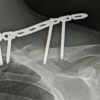

A 30-year-old right-hand dominant male was evaluated in the orthopedic clinic 9 days after his injury. He was the passenger in a motor vehicle collision where his car was hit by another car going about 30 miles/h, and his car flipped over a curb. He was able to self-extricate from the motor vehicle. He was seen in the local emergency department (ED) and diagnosed with a left shoulder inferior (subacromial) distal clavicle dislocation with a displaced scapular spine fracture (Fig. 1-4). Other workup in the ED, including CT of his chest/abdomen and pelvis, were negative for any other injuries. It was also noted that he had an Os Acrominale. When he was evaluated in the orthopedic clinic, his inferior clavicle dislocation was noticed to be a mechanical block to abduction and forward elevation. He was also having significant pain in the lateral shoulder radiating down the ipsilateral ribs. Due to his age, activity level, pain level, and restrictions in range of motion, he was indicated for surgery.

During the surgery, he was placed in a lateral position on a bean bag with his arm in a Trimano arm positioner (Arthrex, Naples, Florida). A 6 cm horizontal incision was made just distal to his scapular spine. The posterior deltoid was released from the scapular spine, leaving a 1 cm cuff for later repair. The supraspinatus and infraspinatus were gently elevated from the superior and inferior aspects of the scapular spine with a wood-handle AO elevator to access the fracture site, with care taken to protect the suprascapular nerve and artery pedicle. An attempt was made to reduce the scapular spine fracture, but anatomic reduction was not possible. It was thought that the inferiorly dislocated clavicle was blocking the reduction. An attempt at a closed reduction of the AC joint was unsuccessful. Therefore, a 3 cm horizontal incision was made over the AC joint. The superior AC joint capsule was incised horizontally for later repair. The distal clavicle was controlled with a small point-to-point reduction clamp and a small Hohman was used as a shoehorn to reduce the inferior clavicle dislocation with medial traction from the clamp. Concentric AC joint reduction was confirmed with C-arm fluoroscopy. After the reduction of the AC joint, the scapular spine was easily reduced to an anatomic position. Two 3.5 mm Arthrex cannulated headless compression screws were placed perpendicular to the fracture line. Then, a 2.7 mm Synthes locking plate was placed on the inferior surface of the scapular spine, and multiple locking screws were placed. Next, an Accumed contralateral side clavicle plate was placed on the superior surface of the scapular spine and two locking screws were placed on each side of the fracture. Dual plates were used in order to increase the points of fixation on the thin shelf of the scapular spine. After the scapular spine was fixed, the distal clavicle was evaluated for stability. The AC joint remained stable to superior/inferior translation and was horizontally stable after the open reduction. It was deemed that the injury represented a capsular injury and the coracoacromial (CA) and coracoclavicular (CC) ligaments were still intact. The AC joint capsule was then repaired with a pants-over vest suture configuration with a 0-vicryl suture in order to imbricate the superior capsule. A 1.9 Arthrex double-loaded fibertak anchor was then placed in the acromion. Each limb of the suture was then krakowed along the superior capsule and tied down to supplement the AC joint capsular repair. His rehab protocol consisted of a sling for 6 weeks. He started pendulum range of motion at the 4-week mark from his surgery date then transitioned to passive range of motion and active range of motion under the guidance of in-person physical therapy. At 9 weeks from surgery, he demonstrated near-complete union of his scapular spine fracture and maintenance of reduction of his AC (Figs. 5-7). At that time, he had no tenderness to palpation of his fracture site or AC joint, so he was allowed to return to work as a line assemblyman. He was also cleared for all activities at 9 weeks post-operative. He started strengthening of the shoulder rotator cuff and periscapular muscles at the 10-week mark from his surgery. At the 3-month post-operative visit, his range of motion was noted to be excellent, with full and symmetric forward flexion, external rotation, and internal rotation (Figs. 8-10). At his 10-week and 3-month follow-up time point, there was no tenderness to palpation at the scapular spine or AC joint. At the 3-month mark, he also had full strength of his rotator cuff, deltoid, and periscapular muscles. He is quite pleased with his functional result and is back to doing all activities he was doing before injury.